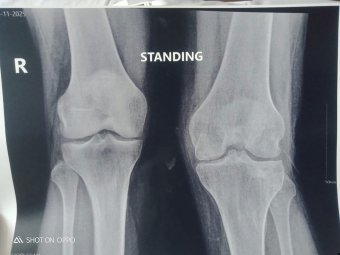

صورة الأشعة السينية تظهر حالة ساق أحمد طارق